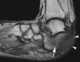

Trophic ulcer of soft tissue with underlying destruction